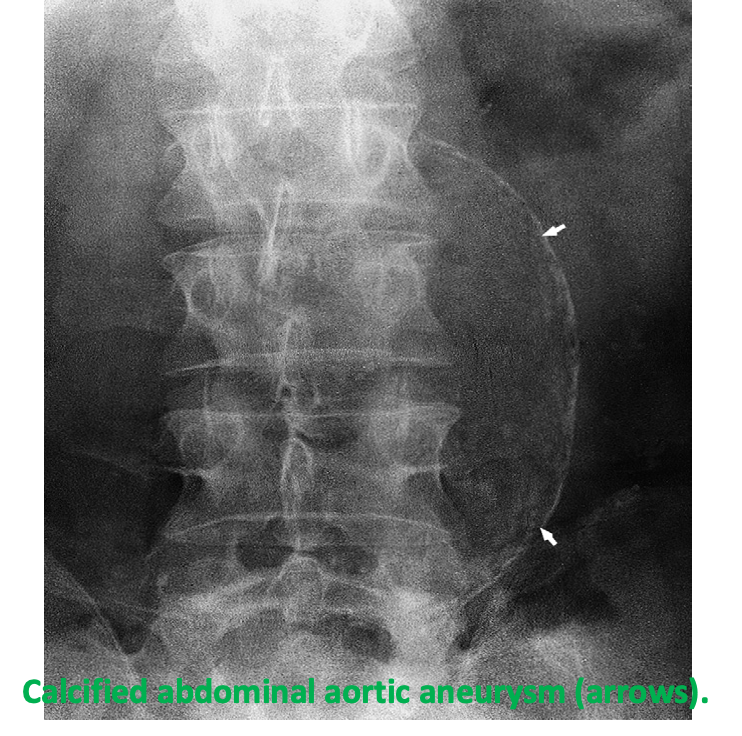

occurs in association with atheroma, and generally has a curvilinear appearance. Calcification is frequently present in the walls of abdominal aortic aneurysms.